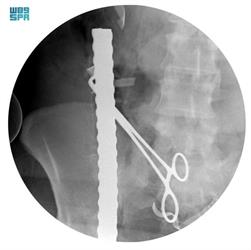

And it showed that the first skewer penetrated the right part of the thigh area in line with the secondary and primary femoral artery and vein with the abdomen, along the major iliac arteries, all the way to the arteries of the right kidney and settled along the duodenum, resulting in a slight injury to the duodenum, while the second skewer penetrated the lower abdominal area below the navel, causing It injured the small intestine in 4 areas and settled in the upper part of the stomach following penetrating the back and front wall of the stomach. As for the third skewer, it was found that it penetrated the pelvis from the left side, which led to a double fracture on that side of the pelvis and settled along the spine without penetrating it.

She pointed out that the first skewer was extracted following controlling the major arteries, while the other two skewers were removed very carefully so as not to affect the organs surrounding the affected area with the restoration of the affected organs as a result of this injury.